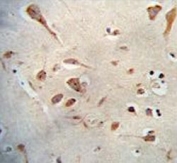

IHC staining of FFPE human cortex tissue with Neuroserpin antibody at 5ug/ml. Required HIER: steamed antigen retrieval with pH6 citrate buffer; AP-staining.